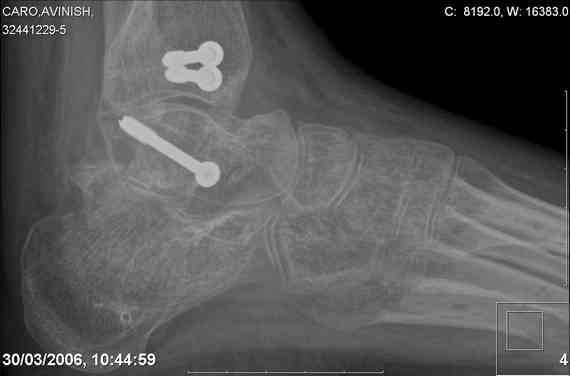

ya by popytalsya sobrat talus anatomichno,seichas pozdno operirovat

iz za oteka,po etomy distrakziya apparatom budet optmalna.Posyalu vam

podobyai moi sluchai.